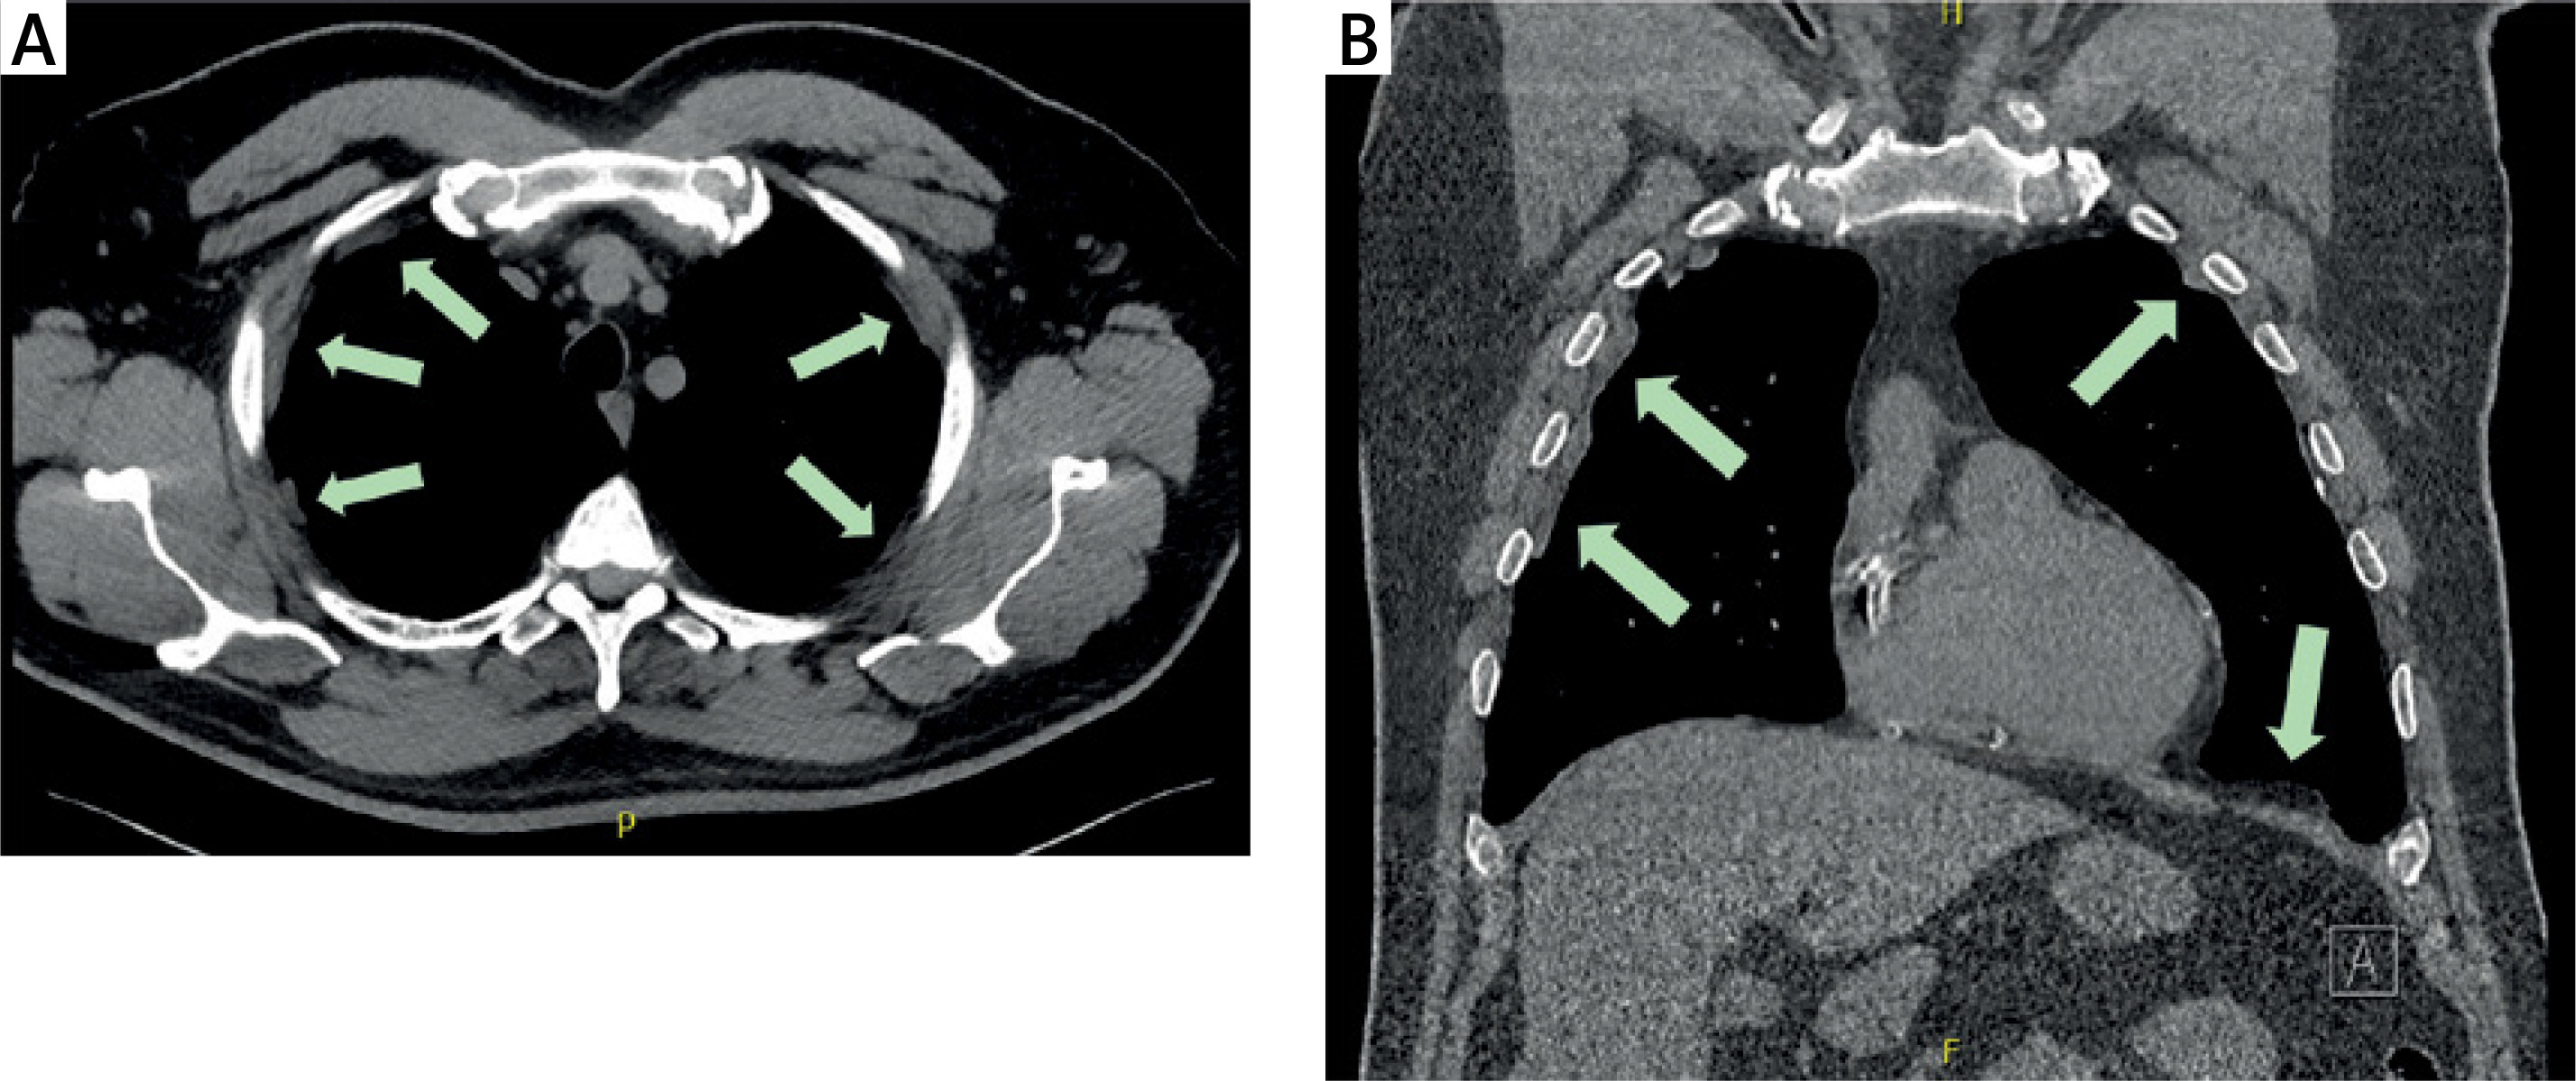

Figure 2

A – A section of the parietal pleura with representative calcified plaques, resected for histological examination. B – Postoperative chest X-ray showing no evidence of pneumothorax or hemothorax